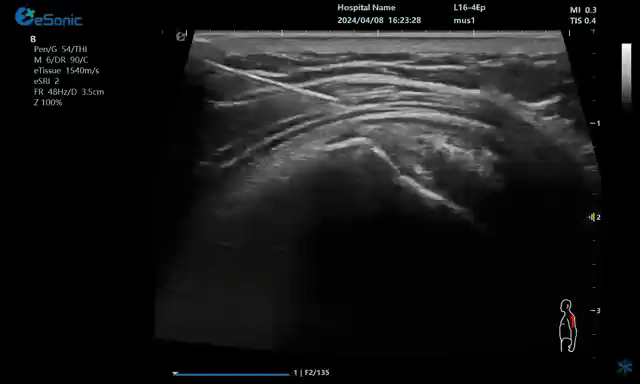

注射麻醉药